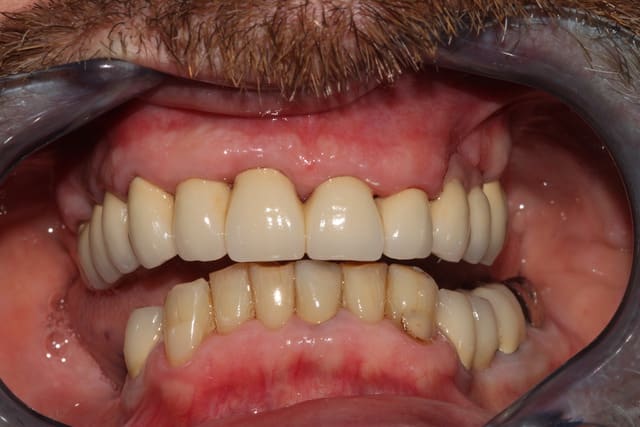

Du coup, pour finir:

-En janvier, c'est reparti: reprise de traitement 12 13 14. Comme je le disais, les RCR 15 16 sont en bon état, les endos asyptomatiques même si pas parfaites: je n'y ai pas touché, l'avenir me dira si j'ai eu raison.

Inlays-core 12 13 14, j'aurais pu réaliser des RCRs mais je ne me sentais pas de paralléliser les 9 piliers à l'oeil.

Le jour de l'empreinte des IC, on prend également une empreinte alginate du bridge pro en place.

Ainsi, par CFAO et en se basant sur les tissus mous périphériques, le labo nous a confectionné un duplicata du bridge pro en résine usinée, qui nous servira à enregistrer la RIM définitive: je n'aurai aucune retouche à y apporter.

Puis classique essayage d'armature (parfaite, merci le labo), et pose. Réglages occlusaux le lendemain.

Pano de contrôle (où je m'aperçois que j'avais laissé un morceau de Fuji entre 36 et 37, honte sur moi, d'où l'intérêt de la radio).

Photos de l'occlusion avant les réglages occlusaux, tout juste sorti du labo. J'ai diminué les contacts sur la 23 en entrée de cycle, et sur la 21 en incision. (bleu en statique, rouge en cycles masticatoires)

Pose des implants prévue pour cet été, donc couronnes vers Noël probablement.

Je peaufinerai probablement encore un peu l'occlusion dans 6 mois, lorsqu'on posera 45 46.